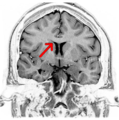

Coronal T2 (grey scale inverted) MRI of the brain at the level of the caudate nuclei emphasizing corpus callosum